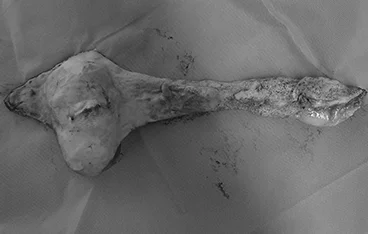

외이도 종괴, 외이염&중이염&내이염

TECA+LBO / VBO

• TECA+LBO 수술 전

TECA+LBO 수술 후

• VBO